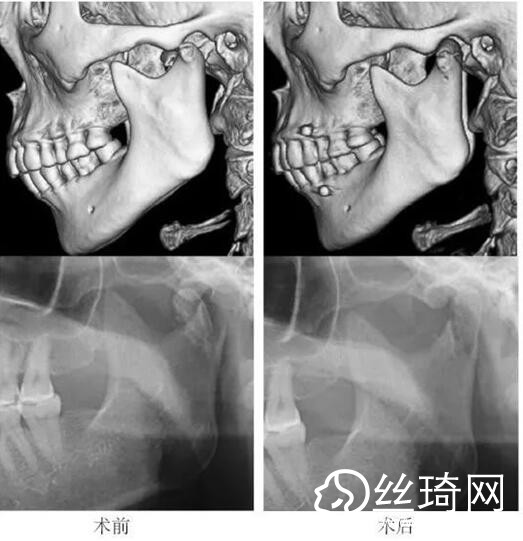

在106側(cè)中,髁突高位矢狀骨折46側(cè),中位髁頸骨折26側(cè),低位髁頸下骨折34側(cè)。髁突高位矢狀骨折及中位髁頸骨折均經(jīng)耳屏前徑路復(fù)位;34側(cè)低位髁頸下骨折中,經(jīng)耳屏前徑路復(fù)位13側(cè),頜下徑路復(fù)位19側(cè),頜后徑路復(fù)位1側(cè),穿腮腺徑路復(fù)位1側(cè)。髁突高位矢狀骨折復(fù)位后以1~2枚可吸收長螺釘固定(圖1)[3],采用的可吸收內(nèi)固定系統(tǒng)為BioSorb(ConMed Linvatec,芬蘭)、Inion OTPS(Inion,芬蘭);規(guī)格:直徑2 mm,長度15~20 mm。中位髁頸骨折及低位髁頸下骨折多以2塊可吸收板固定(圖2)[3],個別病例以1塊或3塊可吸收板固定,采用的可吸收內(nèi)固定系統(tǒng)為BioSorb(ConMed Linvatec,芬蘭)、Grand Fix(Gunze,日本)、Inion OTPS(Inion,芬蘭);規(guī)格:直4孔板,孔徑 mm或2.5 mm,長度21~35 mm,螺釘直徑 mm或2.5 mm,長度7~10 mm??晌蔗敯宓氖中g(shù)操作采用專用器械工具盒,并遵照廠家操作指引進(jìn)行。

82例髁突骨折患者,術(shù)后隨訪6個月至3年,平均年。所有患者術(shù)后未訴明X不適,面型基本對稱,面部肌肉運(yùn)動正常,咬合對位良好,開口度~4.2 cm,平均(±)cm。3例患者開口型輕度偏斜,均為髁突高位骨折,其中2例為粉碎性骨折行骨折碎片摘除,1例為矢狀骨折,以可吸收螺釘固定后,創(chuàng)口感染,隨后行局部清創(chuàng)并取出髁突骨折片及可吸收螺釘,創(chuàng)口愈合良好。96側(cè)髁突骨折中,2例髁頸下骨折術(shù)后復(fù)查CT顯示輕度移位,但患者無功能障礙,持續(xù)觀察,未做特殊處理。其他患者未見明X排斥反應(yīng)及并發(fā)癥。